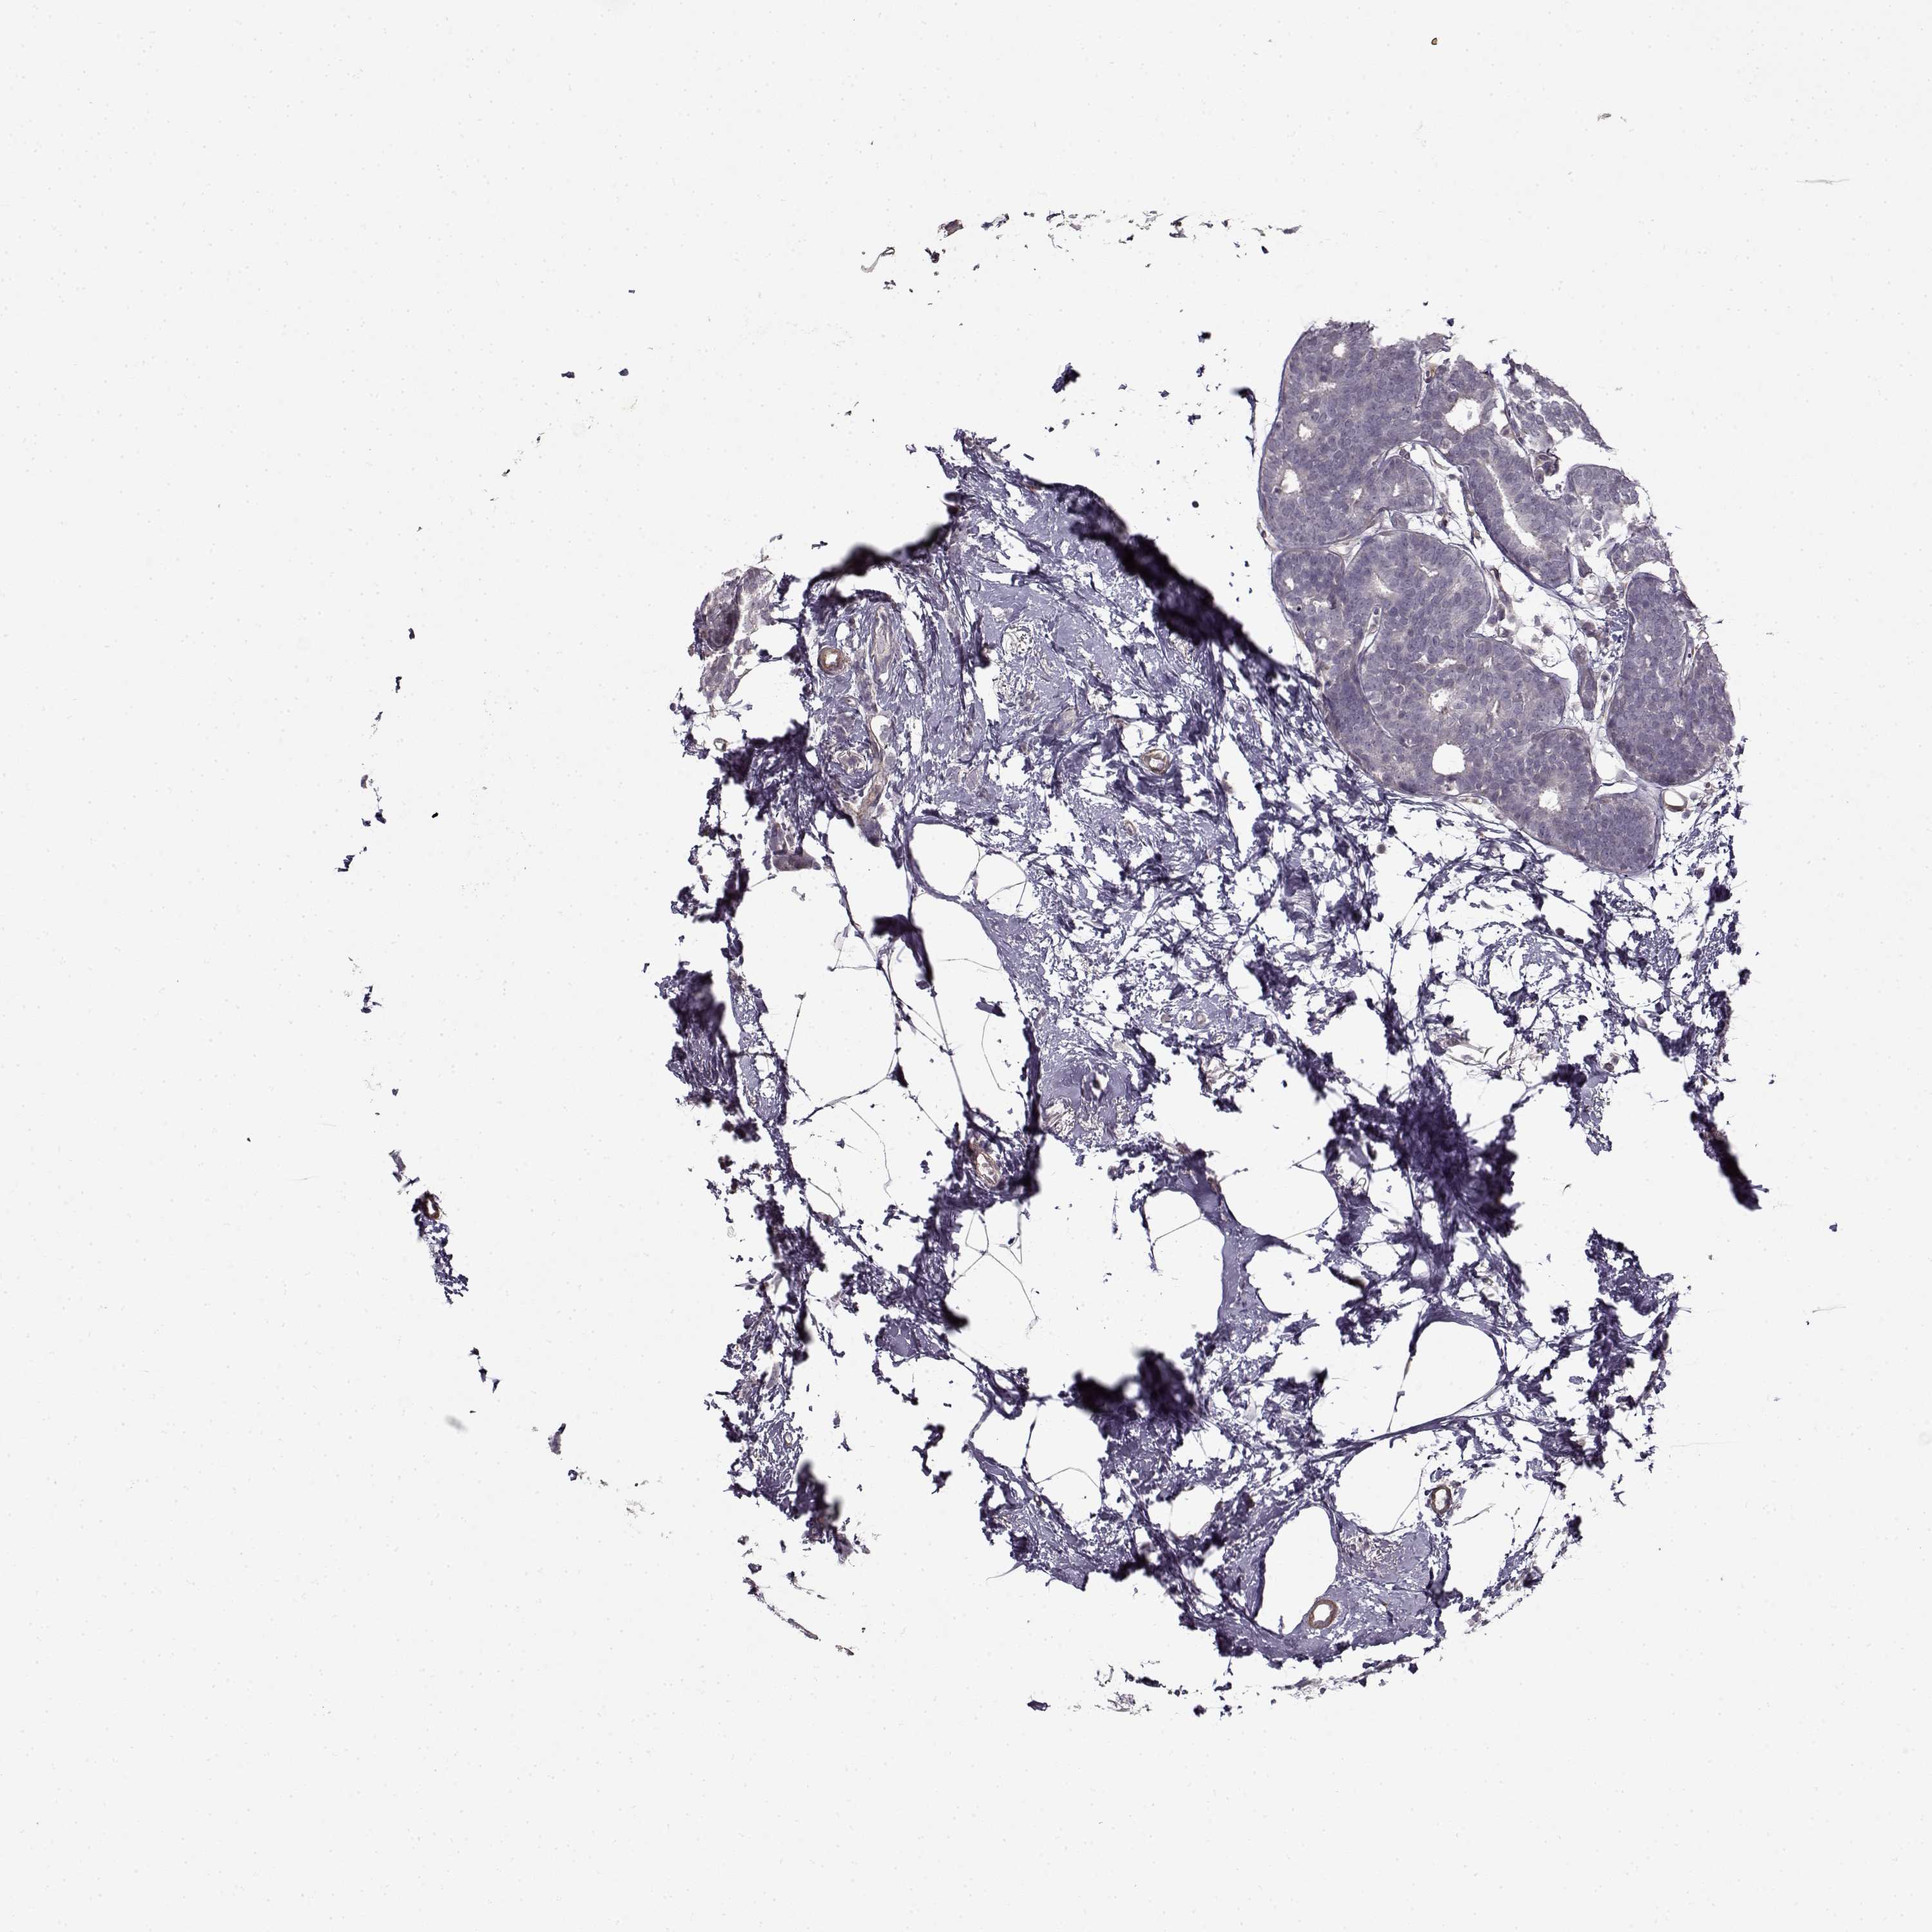

CANCER BREAST CANCER Show tissue menu

BRCA TCGA BRCA VALIDATION PROTEIN EXPRESSION

Breast cancer

Human cancer